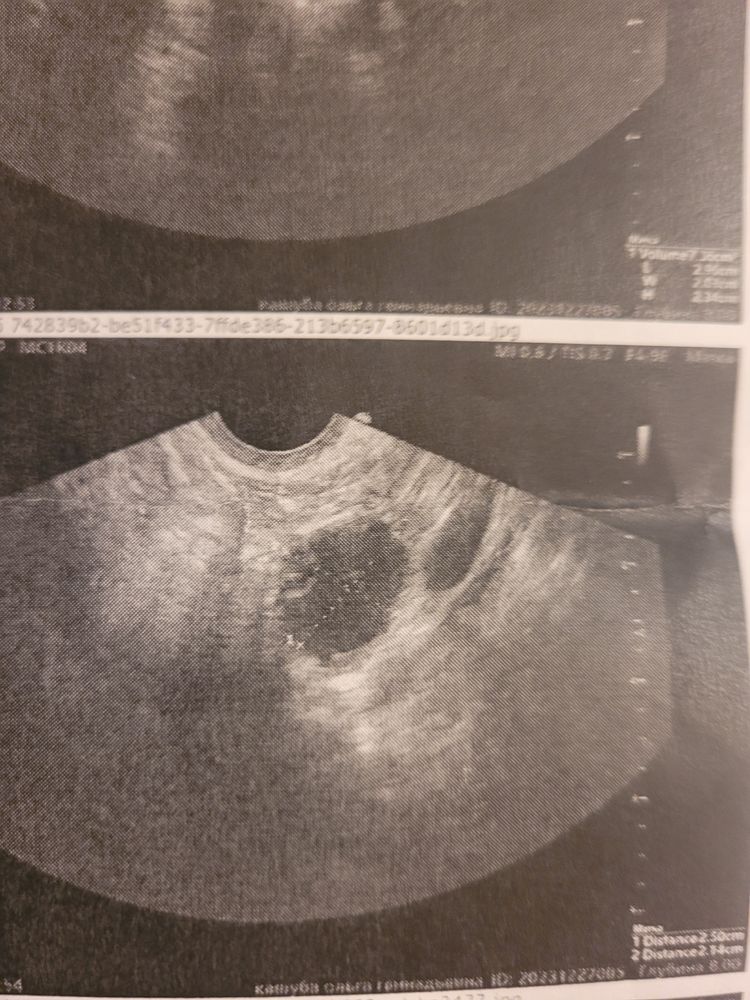

Всем привет. Сегодня была на узи нашли доминантный фолликул 25мм:21мм. Тест на овуляцию и узи прилагаю. Так не хочу кисту :( посмотрите плиз!

У вас же яйценосный бугорок видно даже )))) это значит что уже сегодня завтра фоликул выпустит яйцеклетку ☺️ удачи !

Череппааашка по имени Натааашка , у меня он был и на 20 мм. Боюсь, что он перерос и не будет овульки уже. И это киста. 25 мм и у меня СПКЯ)

Olgita Kashuba, у меня такой же удачно выпустил яйцеклетку 😄 я такую только раз видела, хотя на узи кучу раз была . 25 мм спокойно может еще лопнуть , как и 27. Это все индивидуально . Но вам в любом случае надо через неделю идти смотреть 😄 и у вас в заключении написано вроде что фолик готовится лопнуть . Вы там пресс покачайте ) поактивничайте. Посмотрела у меня был 23 на 22 на 19